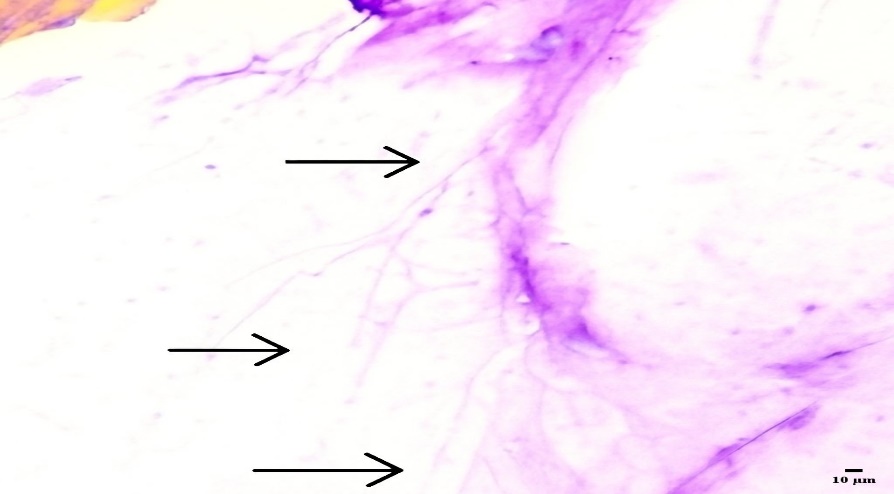

The histological section of hoof tissue infected with candida albicans are shown in fig. 8. The tissue displays abundant fungal structures, including pseudohyphae, blastospores (yeast cells), and hyphal elements, indicating active fungal invasion and tissue disruption [26]. In contrast, Fig. 9 (hoof tissue treated with the optimized nail serum) reveals a marked reduction in fungal structures, with no visible pseudohyphae, blastospores, or hyphae. The hoof tissue architecture appears preserved, indicating that treatment with the serum significantly decreased fungal growth. Similarly, fig. 10 (hoof tissue treated with the marketed formulation) also shows the absence of fungal elements, maintaining the integrity of the tissue. The substantial reduction in fungal colonization observed in fig. 9 demonstrates that the developed nail serum effectively inhibits candida albicans growth. The histopathological results indicate that the serum formulation exhibits antifungal efficacy comparable to the marketed product, thereby supporting its potential use in treating fungal infections of the nail or hoof tissue.

Fig. 8: Histological section of porcine hoof nail tissue infected with Candida albicans

Fig. 9: Histopathology section of porcine hoof nail tissue treated with the optimized nail serum